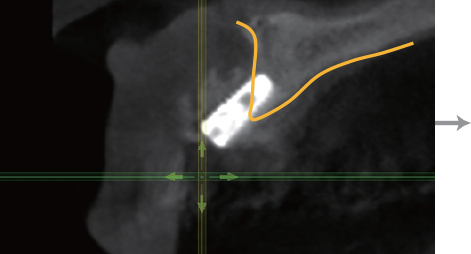

Implant 식립 깊이

전후 Bone Level보다 1~2mm 깊게

BOSS Abutment 높이

전후 치은 높이보다 1mm 낮게